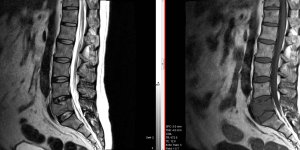

Cauda Equina Syndrome

54 Male presented with 1 week history of low back pain B/L leg pain, worse (L). Reports left leg feels heavy. 7 days ago spoke to GP regarding right leg pain. Reported that the pain had been present for 6 days. GP prescribed codeine 15mg. 3 days later called 111. Was advised to visit A&E. A&E Visit Patient has a history of paranoid [...] Read more